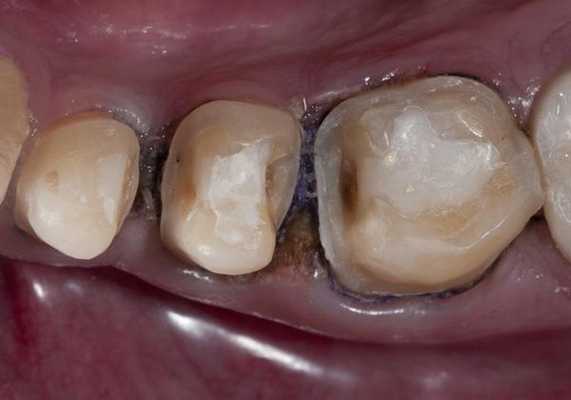

После этого, если есть желание, можно воспроизвести характеристики с помощью композитных красок. Вид после финишной отделки и полировки (рис. 10) .

Окклюзионная коррекция, как правило, минимальна или вообще отсутствует. Вид реставраций через двое суток (рис. 11) .